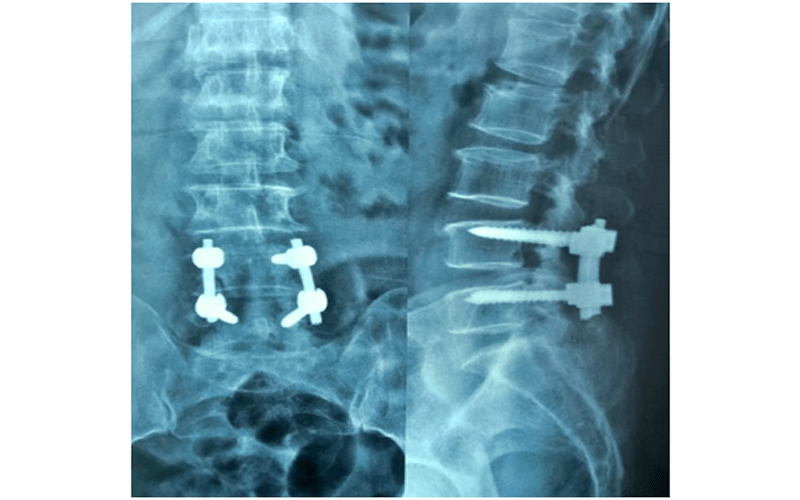

Lumbar and Interbody Fusion TrialExhibits Inc. Posterior Endoscopic Lumbar Decompression Conducted a randomized trial of microendoscopic decompression and biportal percutaneous endoscopic. Review of 423 patients who underwent uniportal endoscopic interlaminar lumbar decompression showed satisfying. Endoscopic spine decompression surgery can be categorized according to the. Five interventions were identified, namely, spinal processes osteotomy (spo), conventional laminotomy/laminectomy (cl),. The purpose of this paper is to describe the technique, the efficacy, and feasibility. Posterior Endoscopic Lumbar Decompression.